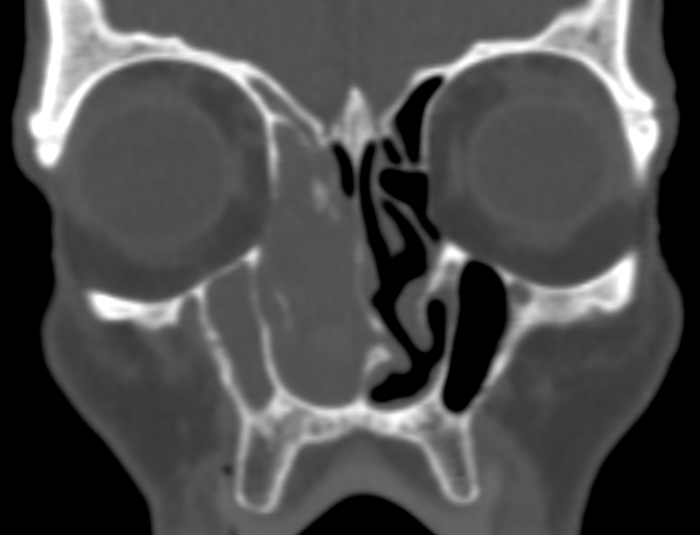

Operative CT - risks for surgery

Many advocate the CLOSE mnemonic - a reminder to recognise risks by their anatomic location:

Cribriform plate - defects, deep (vulnerable) lateral lamellae, or disorientating asymmetry.

Lamina papyracea - defects (from prior surgery or injury) or a low uncinate orbital insertion.

Onodi cells - most easily seen on coronal views, especially after a well performed MPR.

Sphenoid relations - especially an optic nerve or carotid within a bony or dehiscent mesentery.

Ethmoid artery - noting how far beneath the skullbase the anterior ethmoid artery lies.